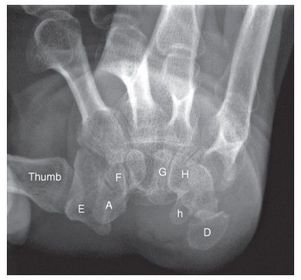

Radial Deviation